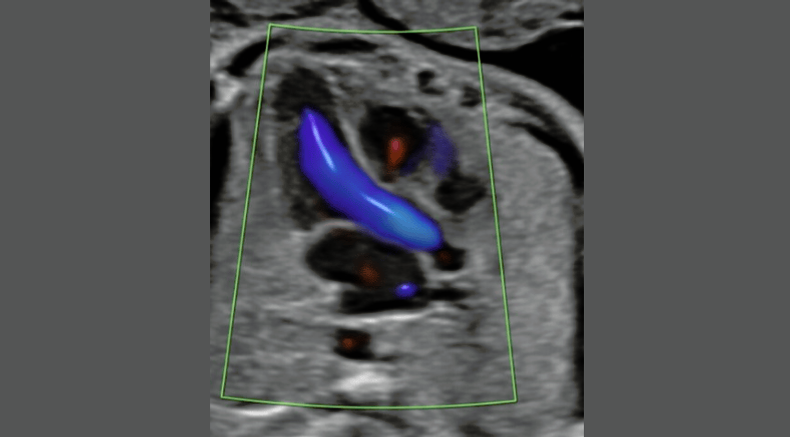

Fetal heart Aortic arch displayed using bidirectional sensitive power Doppler

Chaoui, R. (2021), Evolution of fetal cardiac imaging in 30 years of ISUOG. Ultrasound Obstet Gynecol, 57: 38-42. https://doi.org/10.1002/uog.23551